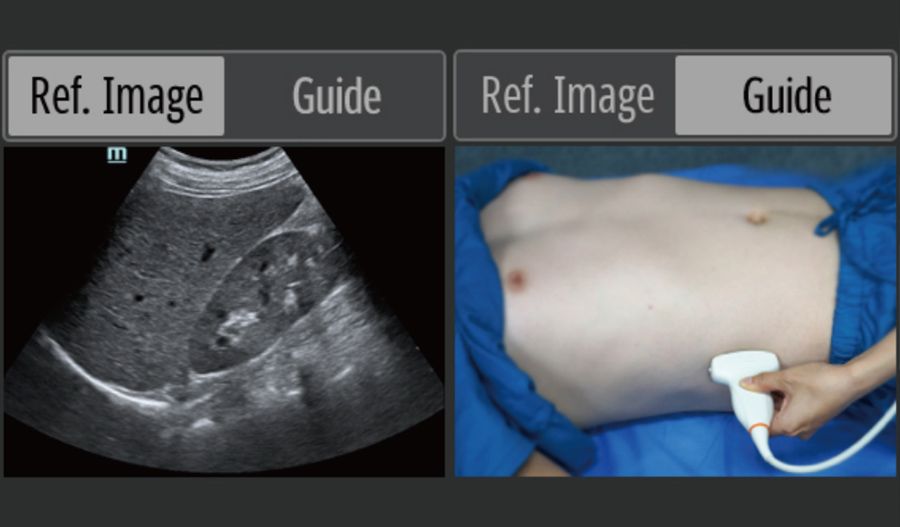

Bak?m Noktas? Ultrasonu (POCUS)

Entegre ultrason fonksiyonlar?, yerinde tan? i?in destek sunar ve uygulamay? tamamen gÞ?lÞ hale getirmek i?in ak?ll? ?al??ma k?lavuzu sa?lar.

- Referans g?rÞntÞler ve Kullan?m k?lavuzlar?

- A?amal? dizi probu: yÞksek ??zÞnÞrlÞk, yayg?n kullan?m